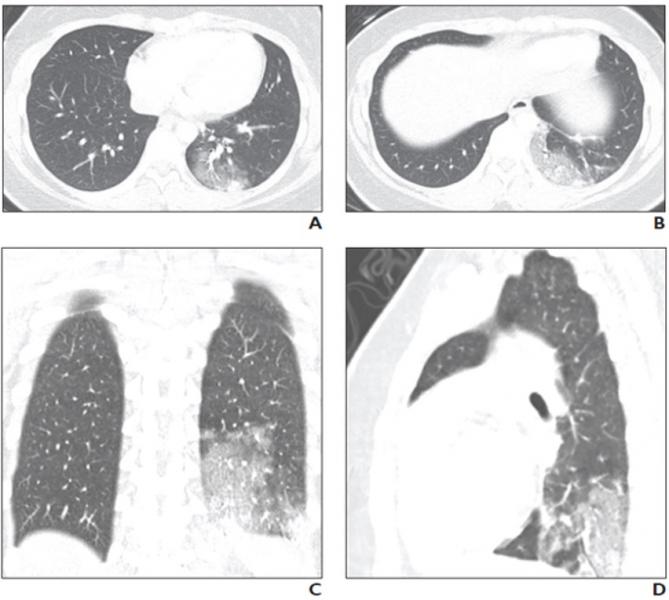

16-year-old girl with coronavirus disease (COVID-19) and known history of tuberous sclerosis who presented with acute hypoxic respiratory distress. Reverse transcription–polymerase chain reaction testing confirmed diagnosis of severe acute respiratory syndrome coronavirus 2 (SARS-CoV-2).

Similarly, while the literature describing chest computed tomography (CT) findings in patients with COVID-19 are more robust than those describing chest radiography findings, only a few articles have reported CT findings of COVID-19 in children.

A study of 20 pediatric patients with COVID-19 reported that the most frequently observed abnormalities on CT were subpleural lesions (100% of patients), unilateral (30%) or bilateral (50%) pulmonary lesions, GGO (60%), and consolidation with a rim of GGO surrounding it, also known as the halo sign (50%).

The authors of this AJR article also pointed to a smaller study of five pediatric patients with COVID-19, where investigators reported modest patchy GGO, one with peripheral subpleural involvement, in three patients that resolved on follow-up CT examination.